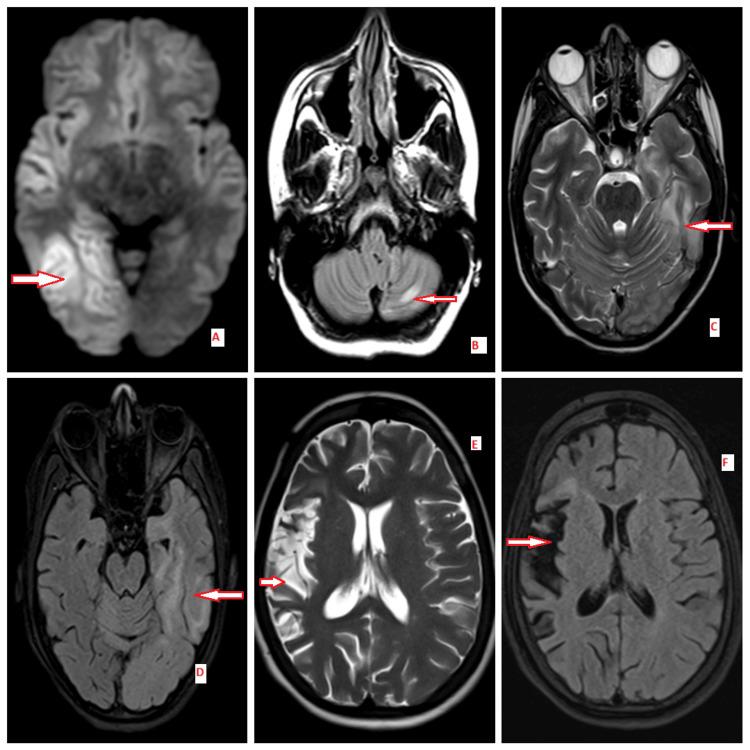

Encephalitis syndromes are acute neurological emergencies characterized by altered sensorium, seizures, movement disorders, and neuropsychiatric manifestations. Autoimmune encephalitis (AE), although rare, necessitates prompt recognition and intervention to reduce morbidity and mortality. This study aimed to examine the clinical features, laboratory findings, radiological characteristics, and treatment outcomes of patients diagnosed with autoimmune encephalitis. This case series presents six patients diagnosed with autoimmune encephalitis and admitted to the Department of General Medicine at the All India Institute of Medical Sciences (AIIMS), Mangalagiri, between January 2024 and January 2025. The mean age of onset was 30.4 years. The cohort included two cases of anti-N-methyl-D-aspartate (anti-NMDA) receptor encephalitis, one case with both myelin oligodendrocyte glycoprotein (MOG) and anti-NMDA receptor antibodies, one case of seronegative autoimmune encephalitis (SNAE) diagnosed based on magnetic resonance imaging (MRI) findings, one case of Rasmussen's encephalitis (RE), and one case of paraneoplastic autoimmune encephalitis (PAE) associated with lung malignancy. This study provides a comprehensive overview of clinical presentations, treatment approaches, and patient outcomes. Early diagnosis and timely initiation of immunosuppressive therapy are crucial for improving patient outcomes. Diagnosis relies on clinical assessment, neuroimaging, and antibody testing, with seronegative cases requiring a high degree of clinical suspicion for appropriate management.

脑炎综合征是急性神经急症,其特征为意识改变、癫痫发作、运动障碍和神经精神症状。自身免疫性脑炎(AE)虽然罕见,但需要迅速识别和干预以降低发病率和死亡率。本研究旨在探讨诊断为自身免疫性脑炎患者的临床特征、实验室检查结果、影像学特征及治疗结果。本病例系列介绍了2024年1月至2025年1月期间在芒加拉吉里全印度医学科学研究所(AIIMS)普通内科住院的6例诊断为自身免疫性脑炎的患者。平均发病年龄为30.4岁。该队列包括2例抗N-甲基-D-天冬氨酸(抗NMDA)受体脑炎、1例同时存在髓鞘少突胶质细胞糖蛋白(MOG)和抗NMDA受体抗体的病例、1例根据磁共振成像(MRI)结果诊断的血清阴性自身免疫性脑炎(SNAE)、1例拉斯穆森脑炎(RE)以及1例与肺恶性肿瘤相关的副肿瘤性自身免疫性脑炎(PAE)。本研究全面概述了临床表现、治疗方法及患者预后。早期诊断和及时开始免疫抑制治疗对改善患者预后至关重要。诊断依赖于临床评估、神经影像学检查和抗体检测,血清阴性病例需要高度的临床怀疑以进行适当管理。